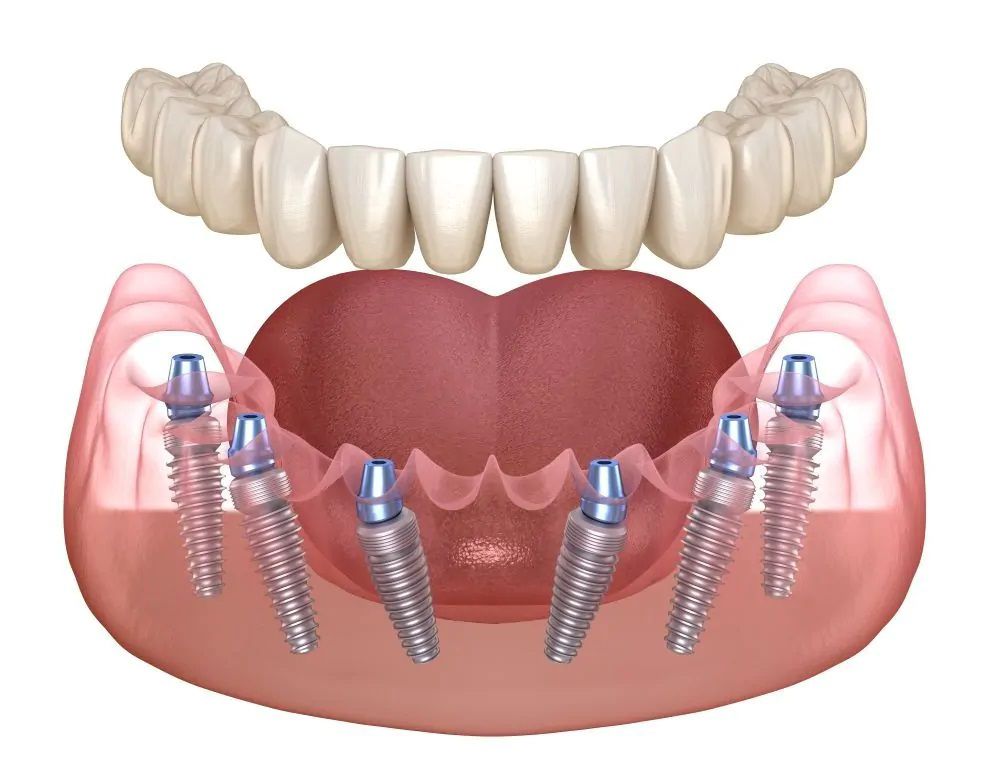

Методика базальной имплантации отвечает всем потребностям пациента и требованиям прогрессивной стоматологии! В отличии от распространенных, в настоящее время, методик ALL ON 4 и ALL ON 6 базальная имплантация не требует "наращивания костной ткани" - импланты подбираются индивидуально под каждого пациента, с учетом особенностей строения его костной ткани.

Применяя методику базальной имплантации мы реализуем концепцию немедленной нагрузки на челюсть (Immediate loading), позволяющей установить протез на импланты в максимально короткий срок - до 3 дней! Методика полностью обеспечивает соответствие современной имплантации и требованиям всех пациентов

all-on-4 и all-on-6 cрок лечения 3-4 дня

Восстановим всю челюсть на 4-х имплантах с несъёмным протезом по швейцарской методике